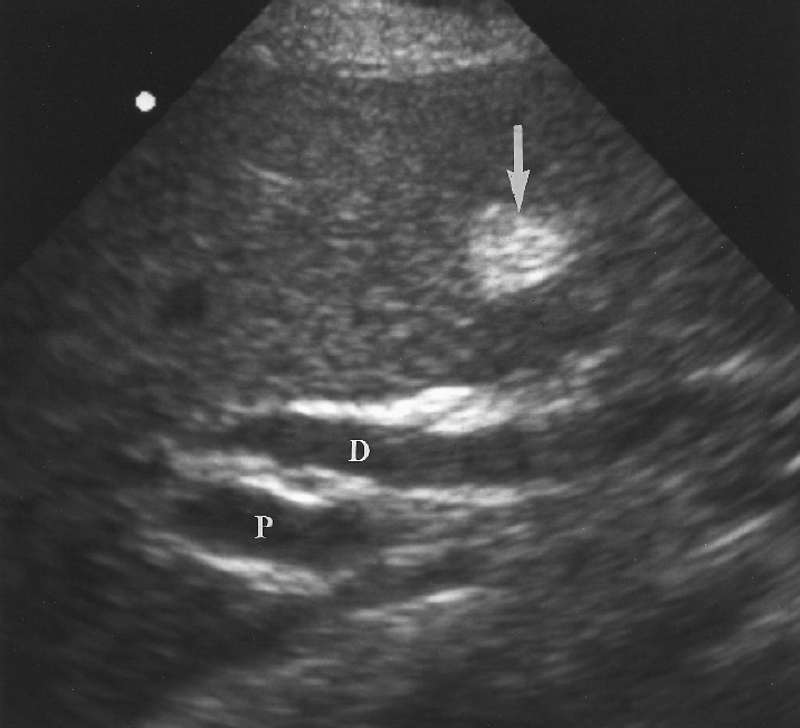

Fatty liver is an acquired but reversible disorder of metabolism. Fatty filtration implies increased lipid accumulation in the hepatocytes.

What is the sonographic appearance of fatty filtration?

Increased echogenicity

Enlargement

of the lobe.

Decreased penetration

Difficult to

image

Increased echo texture